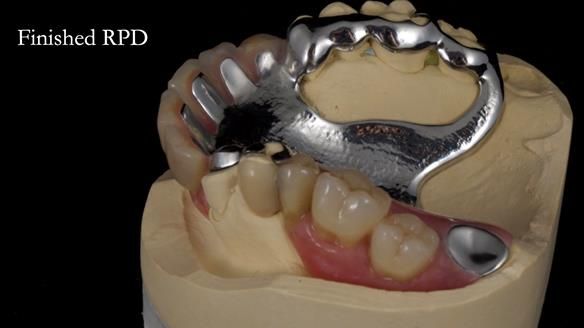

Keith’s case was one of the most challenging and rewarding cases I’ve treated this year. This 64 year old man presented with ill-fitting acrylic partial dentures that lacked stability, retention, and aesthetics. They constantly broke. He had lost the upper front teeth in a road traffic accident in his early 20s. The unopposed teeth had erupted, taking up space. After careful planning, we made a durable, metal-based upper partial denture/splint to address his dental concerns. He loved the outcome.

1. Denture design: A custom cobalt-chromium framework was Scandinavian-designed to maximise stability, protect the remaining teeth, and allow for future additions if needed.

Keith’s denture incorporated a Duracetal shell clasp on upper right first premolar (Myerson), which are designed to be virtually visible, providing a more aesthetic solution while enhancing patient comfort. The Scandinavian-inspired approach, based in modern removable prosthodontic techniques, ensured the denture was not only durable but also visually pleasing. Additionally, the design was carefully planned to allow for future modifications, ensuring that if Keith loses additional teeth, the denture can be adapted rather than replaced entirely.